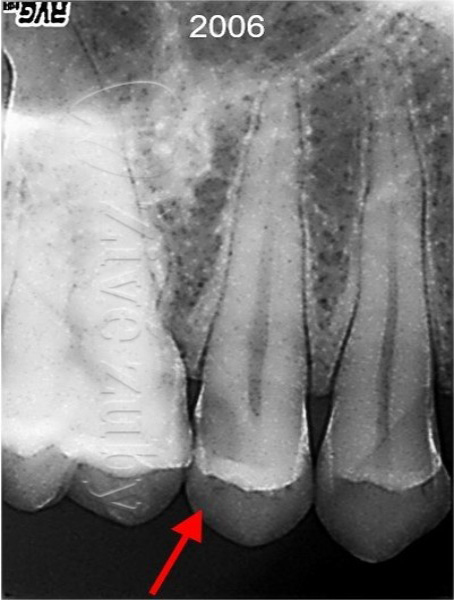

V roce 2006 nás navštívil dospělý pacient s hlubokým zubním kazem, který zasahoval do blízkosti zubního nervu (červená šipka na RTG snímku). Zub reaguje vitálně a pacient si stěžuje na citlivost při jídle.

Pokus o záchranu zubu se zachováním vitality. Obvykle k tomu postačuje zhotovení zubní výplně. Odhadovaná cena ošetření je cca 1000 – 2000Kč (dle rozsahu). První výplň bylo nutné vyměnit cca po 10 letech. V případě selhaní je záložní plán endodontické ošetření (viz varianta B).